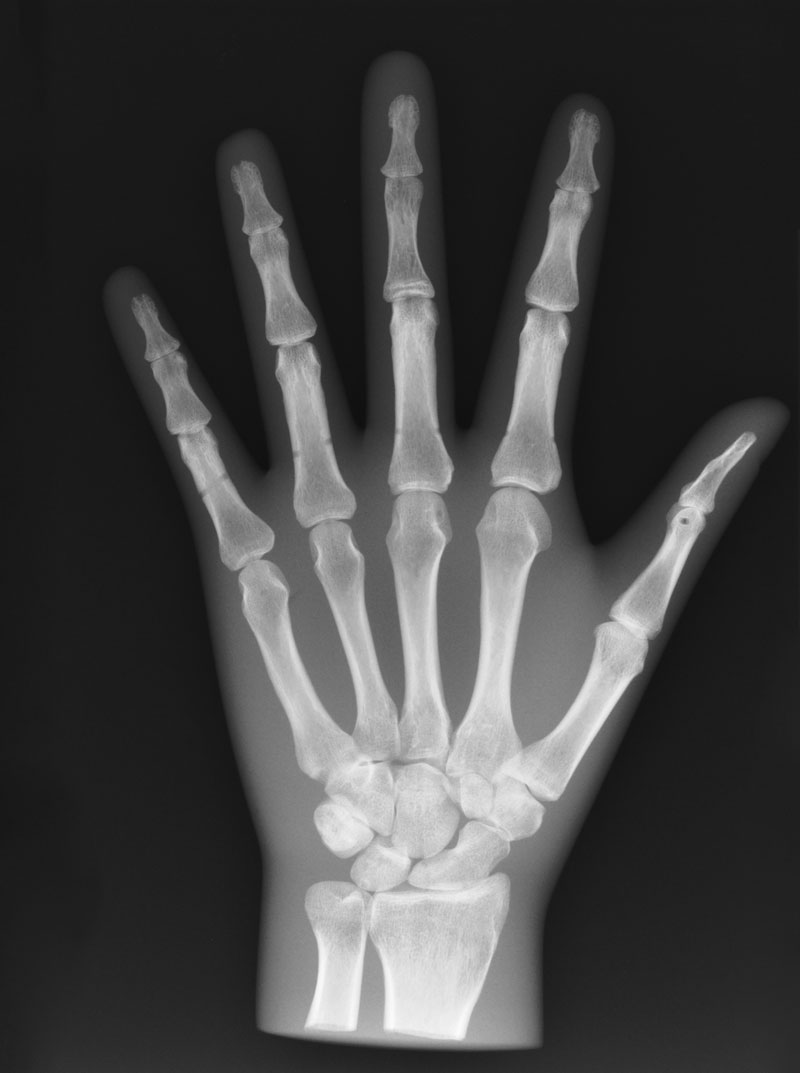

Röntgenphantom Hand, transparent

Unsere weltweit einmaligen Röntgenphantome enthalten echte menschliche Skelett - Teile. Dies gewährleistet erstklassige Aufnahmen und realistische Übungsbedingungen. Eine praxisnahe Röntgen - Ausbildung ist ohne diese Modelle nicht möglich. Jedes Modell wird in handwerklicher Einzelstückfertigung hergestellt und ist jeweils ein Unikat. Bedingt durch die Verwendung von echten Knochen und die individuelle Fertigung weichen die einzelnen Modelle in Größe und Beschaffenheit voneinander ab. Auch erhältlich in undurchsichtiger Ausführung (opak), Art.Nr. 7215.

7210 Röntgenphantom Hand, transparent

2.655,46 € (3160,00 €)

7215 Röntgenphantom Hand, Opak

2.629,41 € (3129,00 €)